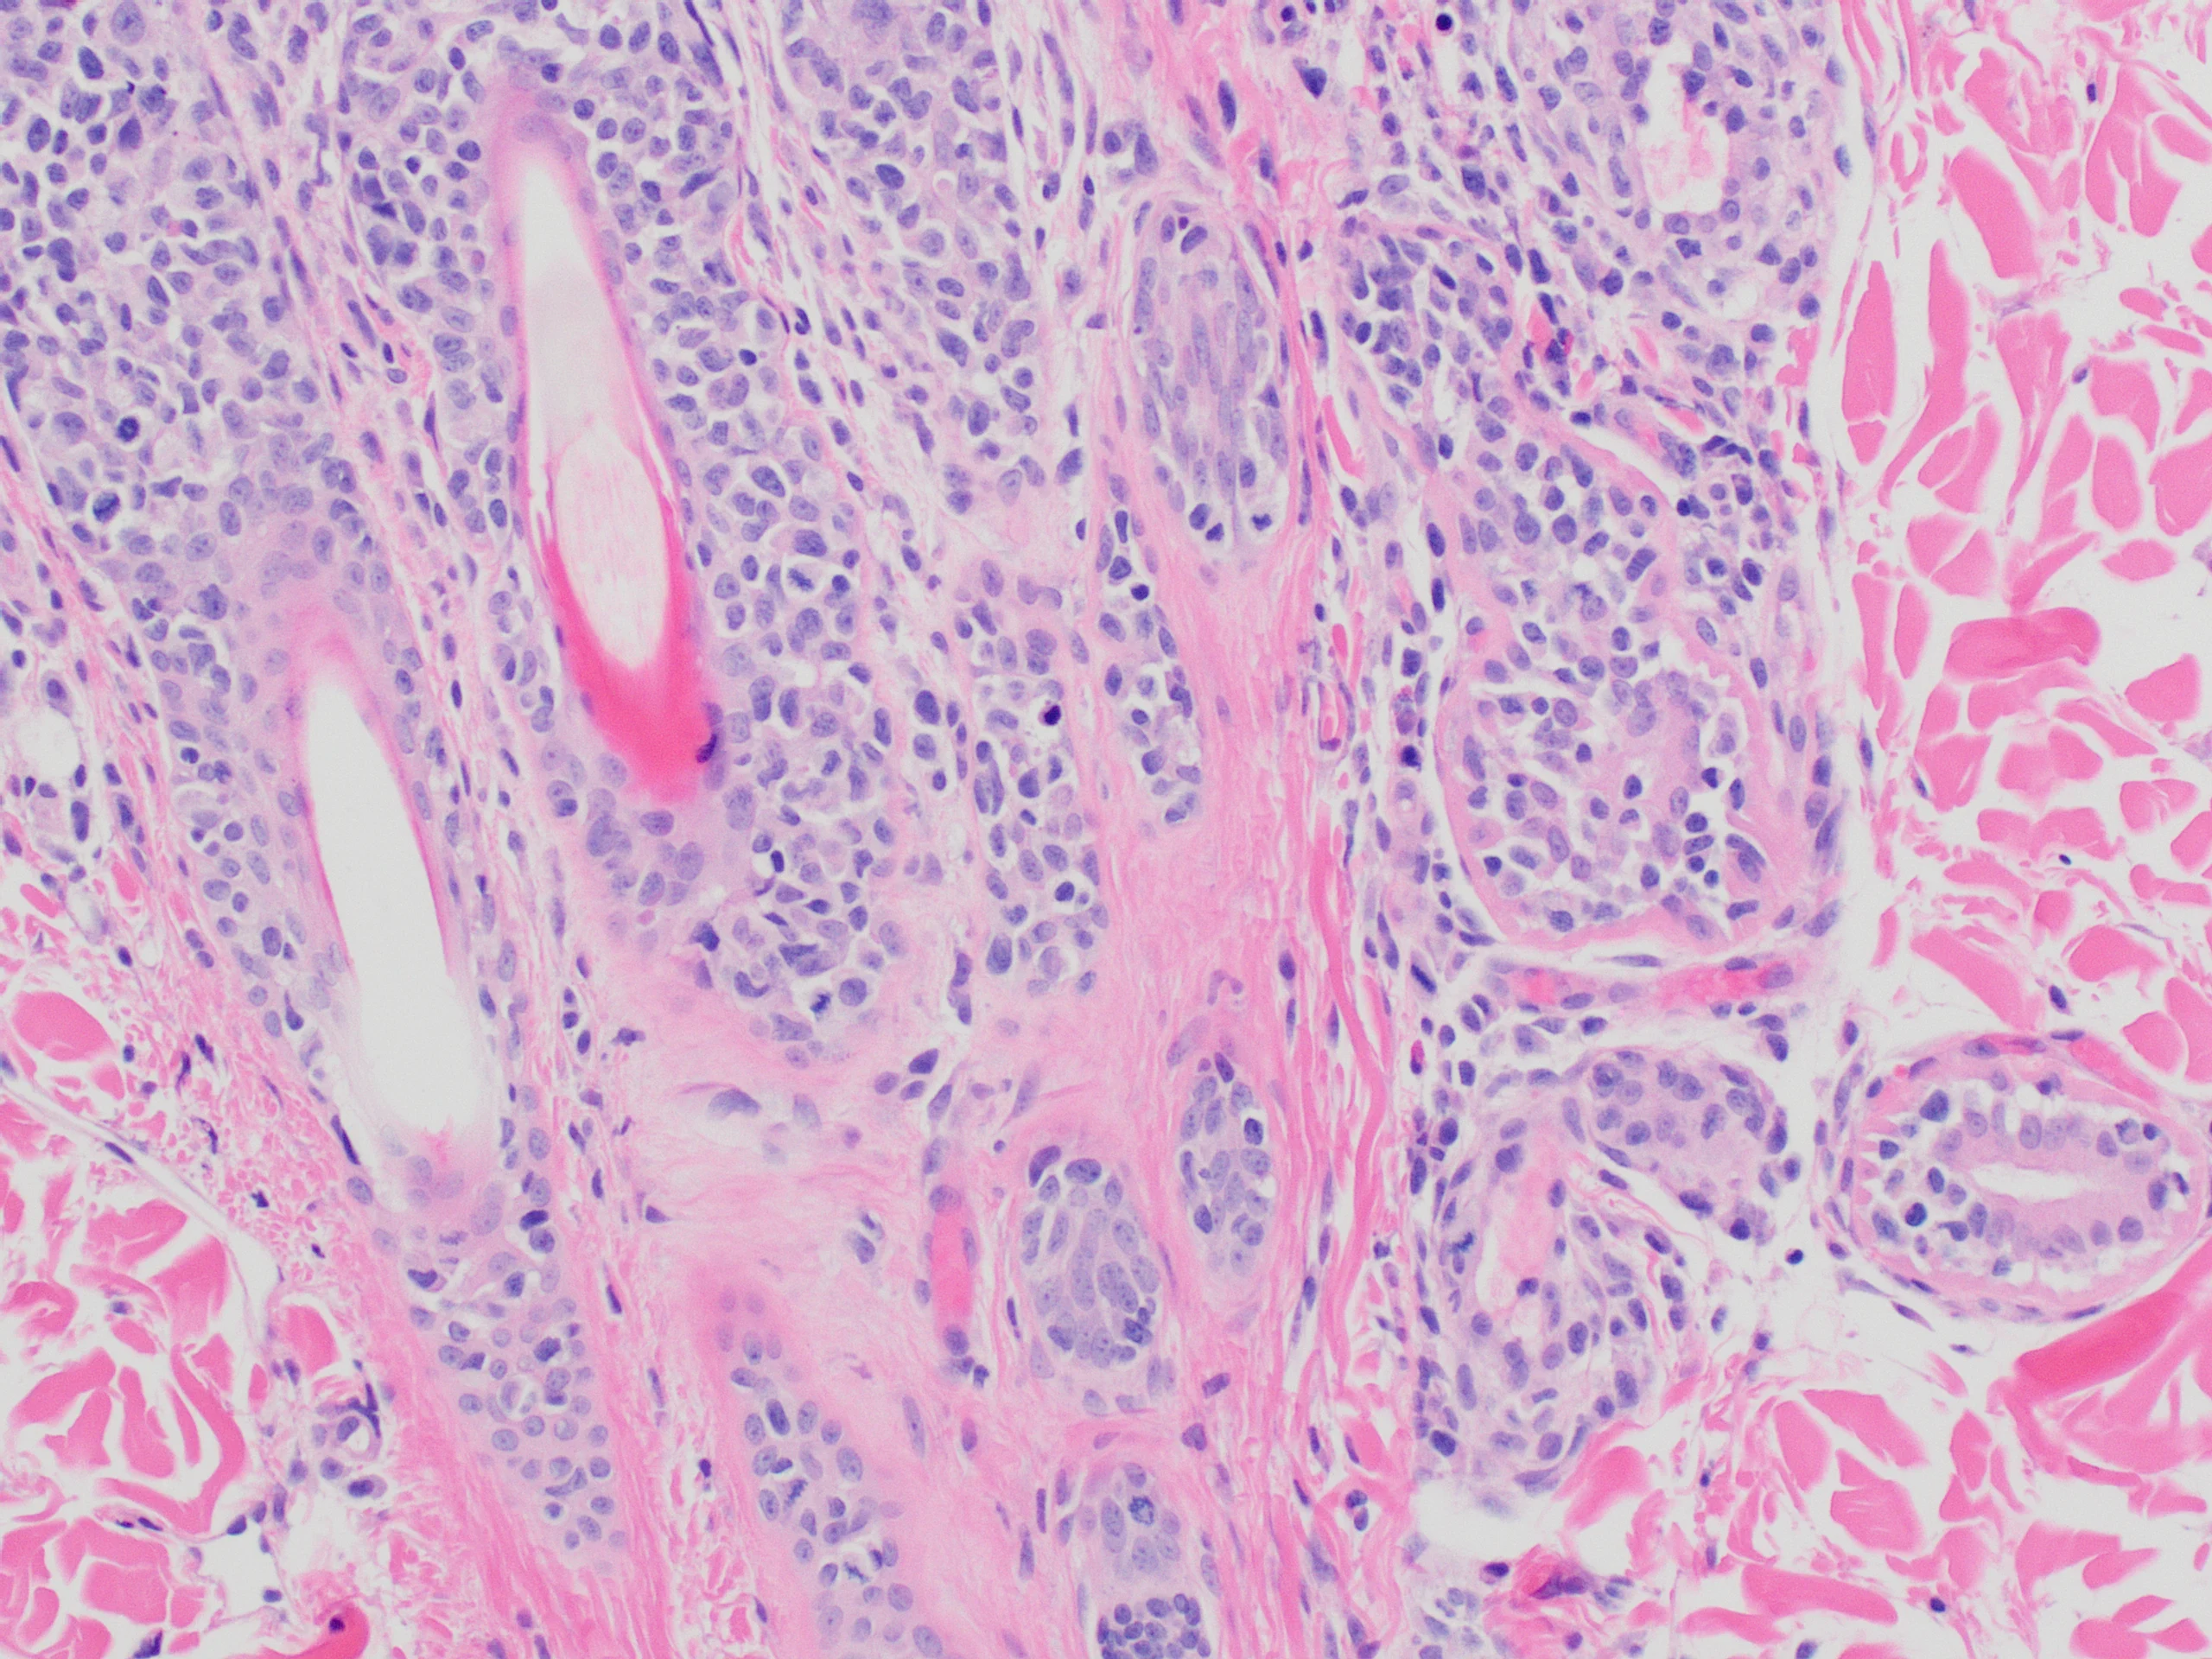

Inflammation is characterized by infiltration of neoplastic T lymphocytes with a tropism for the epidermal or mucosal epithelium, as well as adnexal structures, especially the follicular wall (Figure 4).7,12 Pautrier’s microabscesses (intraepithelial neoplastic lymphocytes diffusely in the epidermis or in aggregates) may be noted.7 Neoplastic lymphocytes that infiltrate apocrine sweat glands occur in 70% of cases and are considered diagnostic (Figure 5).6,7

Neoplastic lymphocytes infiltrating the follicular wall. Image courtesy of Dr. Shannon Martinson

Neoplastic lymphocytes infiltrating an apocrine sweat gland. Image courtesy of Dr. Shannon Martinson